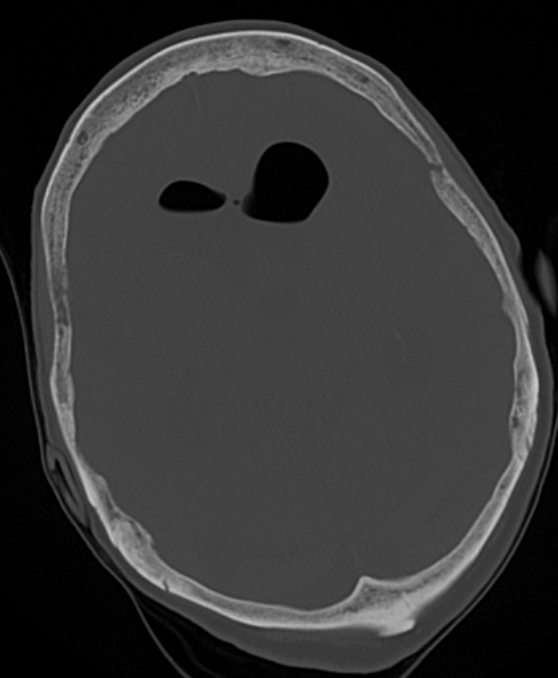

Air has an extremely low density on head CT, and should appear black, no matter how you window the head CT. One of the easiest ways to verify that something dark is air, rather than another hypodense material such as fat, is to look at the CT using the bone window, a setting which shows detail in highly dense structures. Air should remain dark even when viewing the head CT in this way – see the example below.

Did you see the free air? Look at the annotated head CT below to be sure.